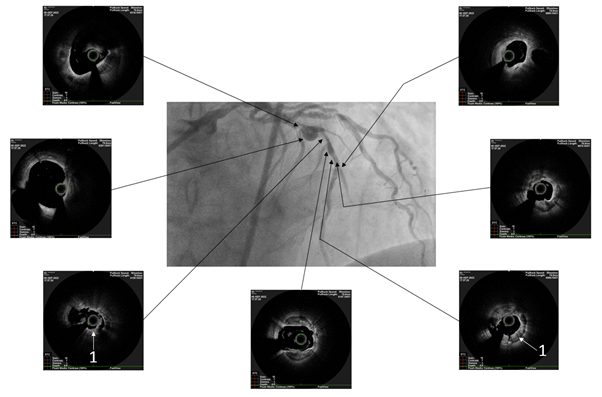

The patient underwent endovascular rotational atherectomy followed by stenting of the affected segments of the coronary arteries. The intervention was carried out under the control of optical coherence tomography (OCT). Initially, the right common femoral artery was punctured under local anesthesia and a 7F introducer was placed. Next, the guide catheter was placed at the mouth of the LCA. The coronarogram revealed 80% calcified stenosis in the terminal LCA OS with a transition to the proximal segment of the LAD and 90% calcified stenosis in the middle segment of the LAD (Figure 1). Using a microcatheter, a conductor was introduced into the apical segment of the LAD. Next, the destruction of calcified atherosclerotic plaques in the LCA and LAD was performed using the Rotablator system of rotational atherectomy (Figure 2), after which, under OCT control (Figure 3), predilatation of the stenotic areas of the LAD with a 2.25x15 mm balloon catheter was performed, followed by positioning and implantation in the area of residual stenoses in the middle segment of the LAD, the proximal segment of the LAD and the OS of the LCA of everolimus drug-eluting stents 3x38 mm and 4x38 mm, respectively. Then, post-dilatation of the stented segments with 3.5x20 mm, 4.5x15 mm balloon catheters and proximal optimization in the LCA OS with a 5x15 mm balloon catheter were performed, achieving a good angiographic result: blood flow in the TIMI-3 arteries. On the control image and OCT control, the stents were fully extended, no signs of dissection were detected, and no residual stenoses were found (Figure 4, 5).

Figure 1 Selective coronary angiography.

A. and B. 80% calcified stenosis in the terminal LCA and proximal LAD segment (white arrows), 90% calcified stenosis in the middle LAD segment (black arrows) and aneurysm in the middle LAD segment with a diameter of up to 6 mm (red arrow); C. RCA is diffusely changed, expanded throughout up to 5-6 mm; VZV is occluded from the orifice (white arrow).

Figure 3 Optical coherence tomography after rotational atherectomy.

White arrows indicate destroyed concentric calcification (1).